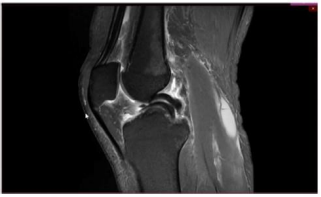

Caso clínico para responder à questão.

Um paciente de 19 anos de idade sofreu entorse do joelho

direito durante agachamento em partida de futebol. Foi

retirado do campo e queixando-se de dor na face interna do

joelho. Foi levado ao hospital mais próximo e, ao ser

examinado, percebeu que não conseguia estender

completamente o joelho. Não conseguia flexionar totalmente

o joelho também. Notaram-se ainda, edema e o sinal da tecla.

Considere que, no caso clínico descrito, foi realizado o exame complementar, conforme apresentado. Essa figura mostra